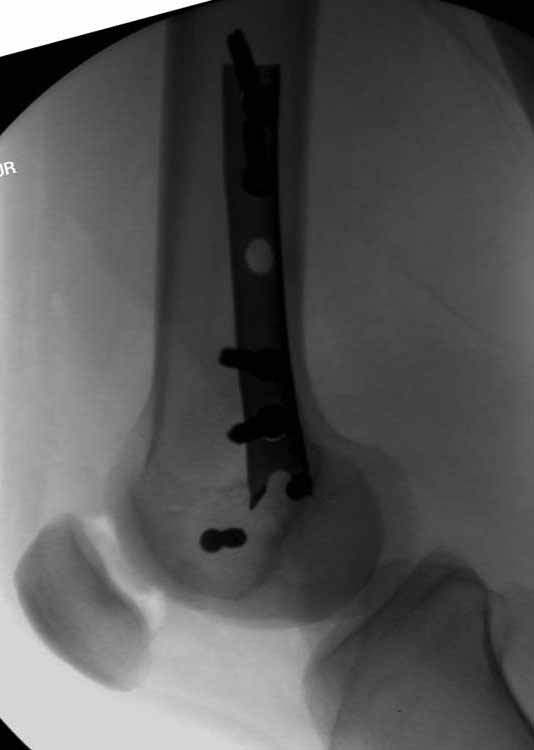

Ответ на эту часть Вашего поста – вложенный файл. Больная оперирована неделю назад по поводу открытого перелома дистального эпиметафиза бедренной кости. После операции она идёт в рентгенкабинет для выполнения послеоперационной контрольной рентгенографии, представленной на слайдах 10 и 11. Узнав, почему её фотографируют, просила передать Вам, Антон, привет.

наружный мыщелок не дорепонироавн - это приводит к вальгусной деформации оси коленного сустава, очень критично для последующей функции.